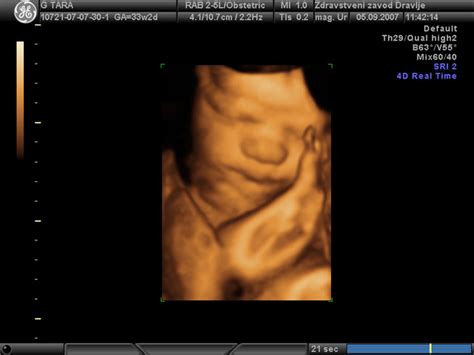

Sprožitev poroda, znana tudi kot indukcija poroda, je medicinski postopek, ki se ga izvede, ko naravni začetek poroda ni mogoč ali pa bi nadaljevanje nosečnosti predstavljalo večje tveganje za plod ali mater. Po 42. tednu nosečnosti oziroma že po 10. dnevu po predvidenem datumu poroda se bistveno poveča tveganje za hude zaplete, vključno s smrtjo otročka v maternici. Zato je ključnega pomena skrbno spremljanje nosečnice po roku. Nosečnico po roku pogosteje pregledujejo, na dva do tri dni, s čimer ocenjujejo stanje ploda in nosečnice. Ti pregledi vključujejo snemanje CTG-ja (kardiotokografija), ultrazvočni in ginekološki pregled.